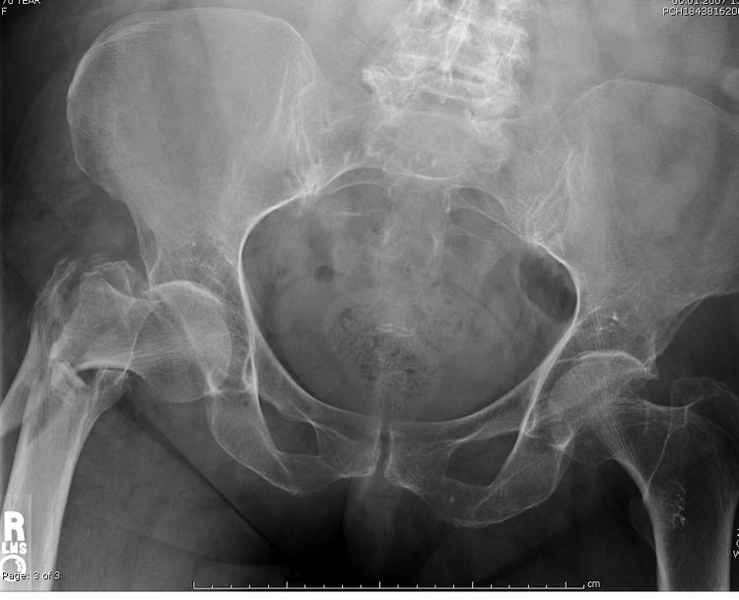

По нашему мнению линия перелома проходит вверху через латеральный отдел шейки бедра, вертельная область состоит из нескольких фрагментов. В таких условиях применить DHS или дистальную бедренную пластину LCP представляется нам сомнительным. Закрытый остеосинтез проксимальным гамма-гвоздем или PFNa невозможен т.к. нет ЭОПа.

Прилагаю Р-ы на вытяжении.